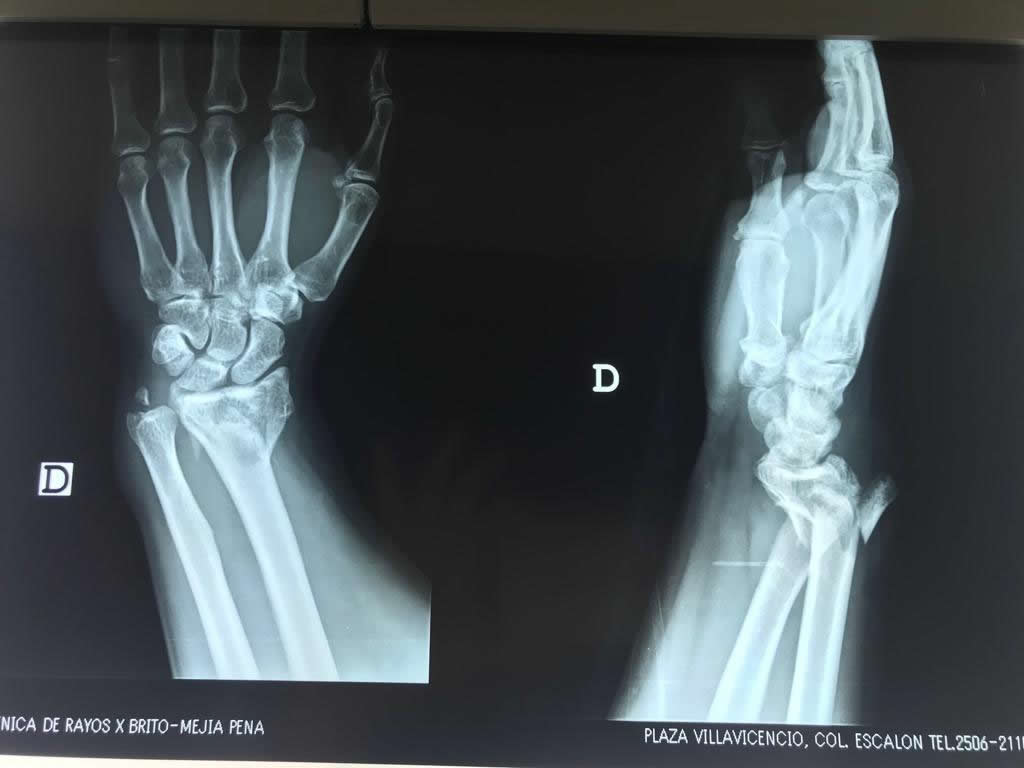

Cirugía de Fémur - Cirugías de Muñecas y Manos

Los procedimientos más comunes en cirugía de la mano son aquellos destinados a reparar traumatismos, incluyendo lesiones de tendones, nervios, vasos sanguíneos, y articulaciones; huesos fracturados; y quemaduras, cortes, y otros daños de la piel.